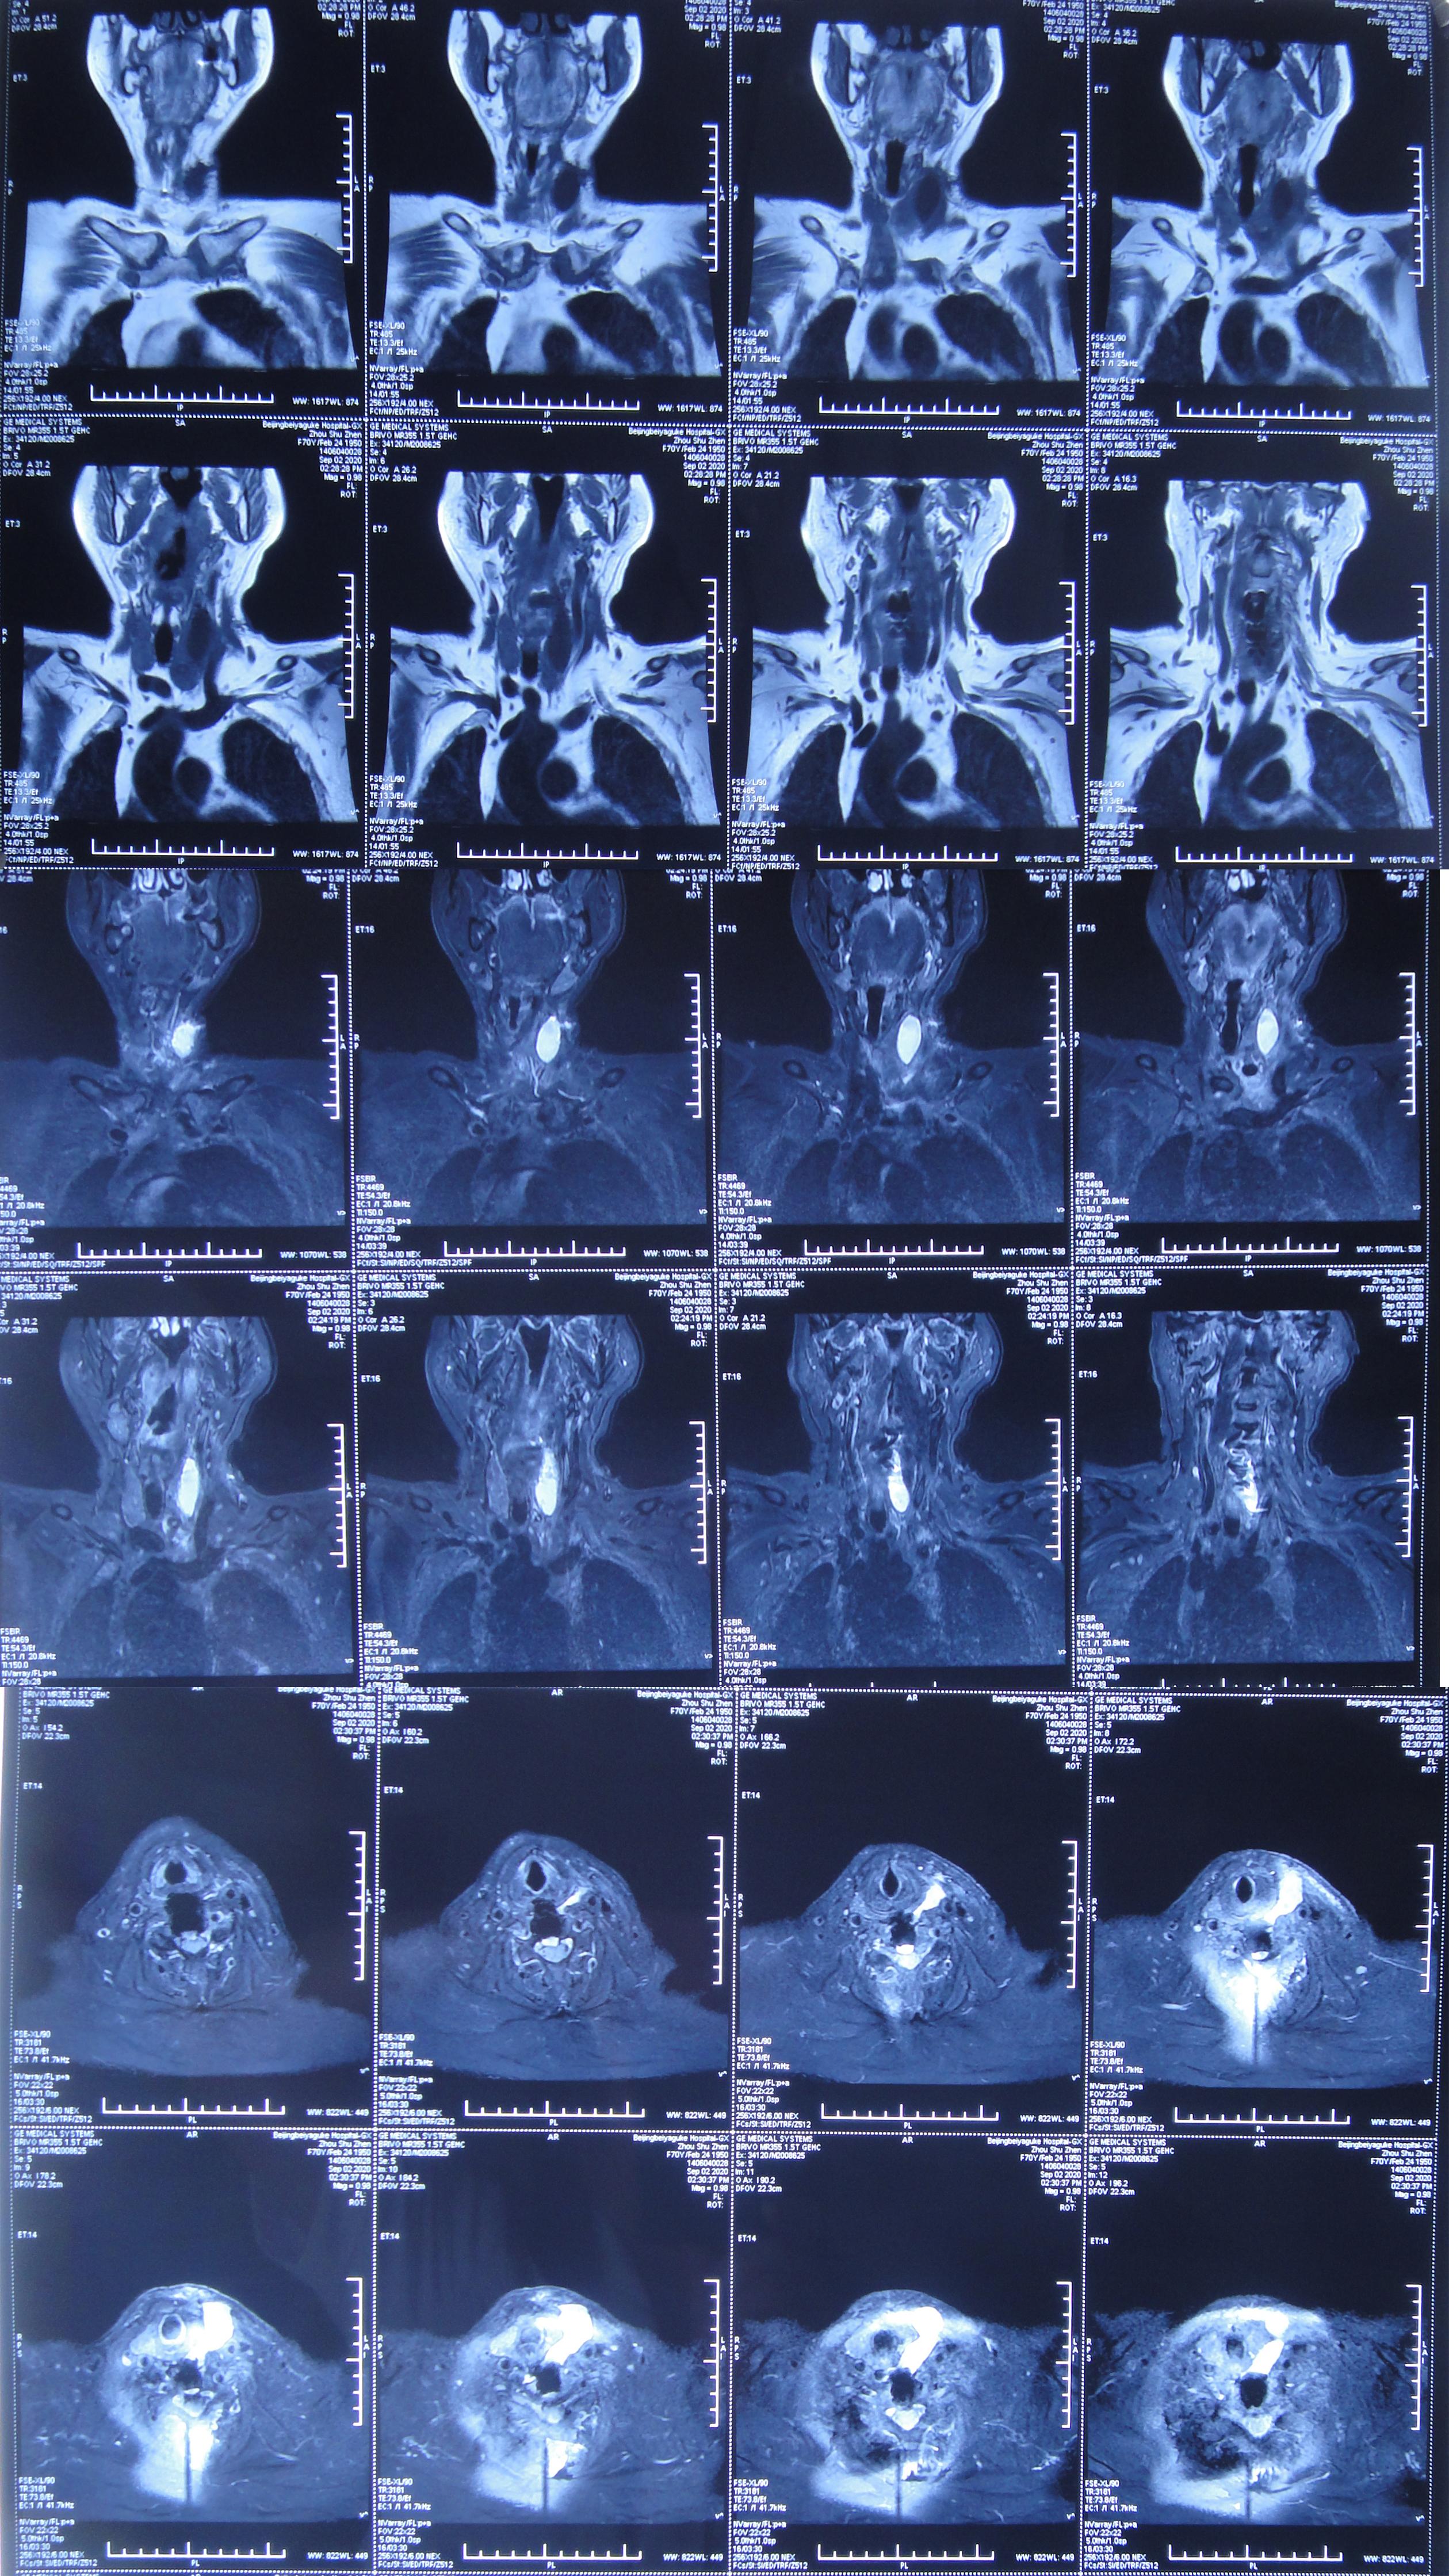

患者因间断性头晕、行走不稳,伴双上肢放射痛,麻木,于2020年4月11日入住北京某三级医院的中医骨伤科,当日查颈椎CT示椎管狭窄性颈椎病(图-1)。

图-1: 2020年4月11日颈椎CT

入院后第二天2020年4月12日查颈椎MR示颈椎病(脊髓型)( 图-2 )。

图-2: 2020年4月12日颈椎MR